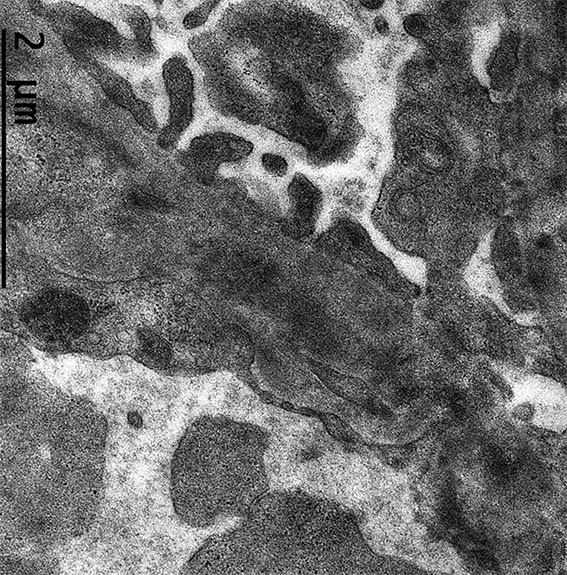

Figure 11. Electron microscopy, original magnification, X2,500. There is endothelial edema and subendothelial electron-dense deposits.

Figure 12. Electron microscopy, original magnification, X4.000. Irregular thickening of the GBM and electron-dense subendothelial deposits.

Figure 13. Electron microscopy, original magnification, X4.000. Subendothelial unorganized electron-dense deposits. Endothelium with loss of fenestrations due to edema.

Figure 14. Electron microscopy, original magnification, X4.000.